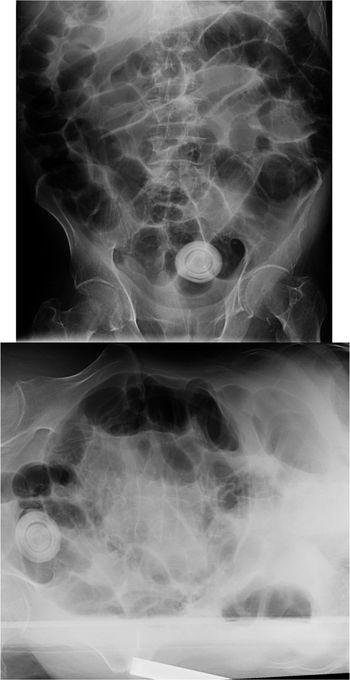

Case History: 36-year-old male presented with weak stream and pain.